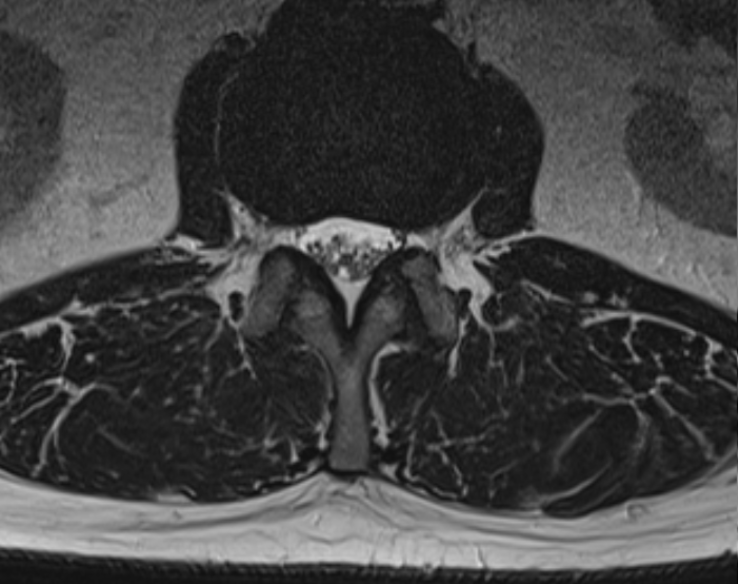

Вот вам классический пример, как делать не надо. Мужчина, 29 лет. Cидячая работа, ремонт дома и стала болеть спина. Да так, что появились стреляющие боли в ногах. На МРТ определяется эктрузия, то есть большое грыжевое выпячивание, которое сдавливает нервный корешок, что и вызывает боль.

Такая картинка сама по себе уже не хорошо. Это не протрузия, которая может вправиться за счет усиления тонуса мышц и исправления осанки. Эструзия возникает на месте разрыва диска, поэтому давить на диск, используя осевые нагрузки или сгибания для проработки мышечного каркаса уже нельзя. В самом позвоночном канале на этом уровне содержится только дуральный мешок, разгрузить его "изнутри" также нет возможности.

Несмотря на это, наш герой решает не идти к врачу, так как панически боится, что тот предложит ему операцию, а идет он к фитнес-тренеру, который специализируется на лечении болей в спине. Фитнес-тренер неадекватно оценивает состояние своего клиента и всего через месяц упорных тренировок пациент возвращается с ухудшением - спина болит постоянно, стреляет до искр из глаз. На МРТ картинка еще более показательная: